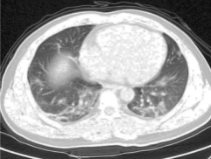

Table 3. Enhancement using dehazing and estimation of illumination for lung images of different datasets

Input Image

Output 1

Output 2

Final Enhanced Image

Lungs-1

Lungs-2

Lungs-3

Lungs-4

Note: This table is showing some lung images intermediate and final enhanced forms.

In Table 3, different dataset lung images' intermediate and final enhanced forms are showing. In the Table 4. we are showing the comparison between the calculated discrete entropy of enhanced images, PSNR, GMSD, and MCSD score for our proposed method as well as for Adaptive Gamma Correction with Weighting Distribution Method (AGCWD). In our proposed enhancement method, Entropy and GMSD score is always better than AGCWD method. High entropy is often desirable for images with complex textures and a lower value of GMSD indicates the improved quality of an image.